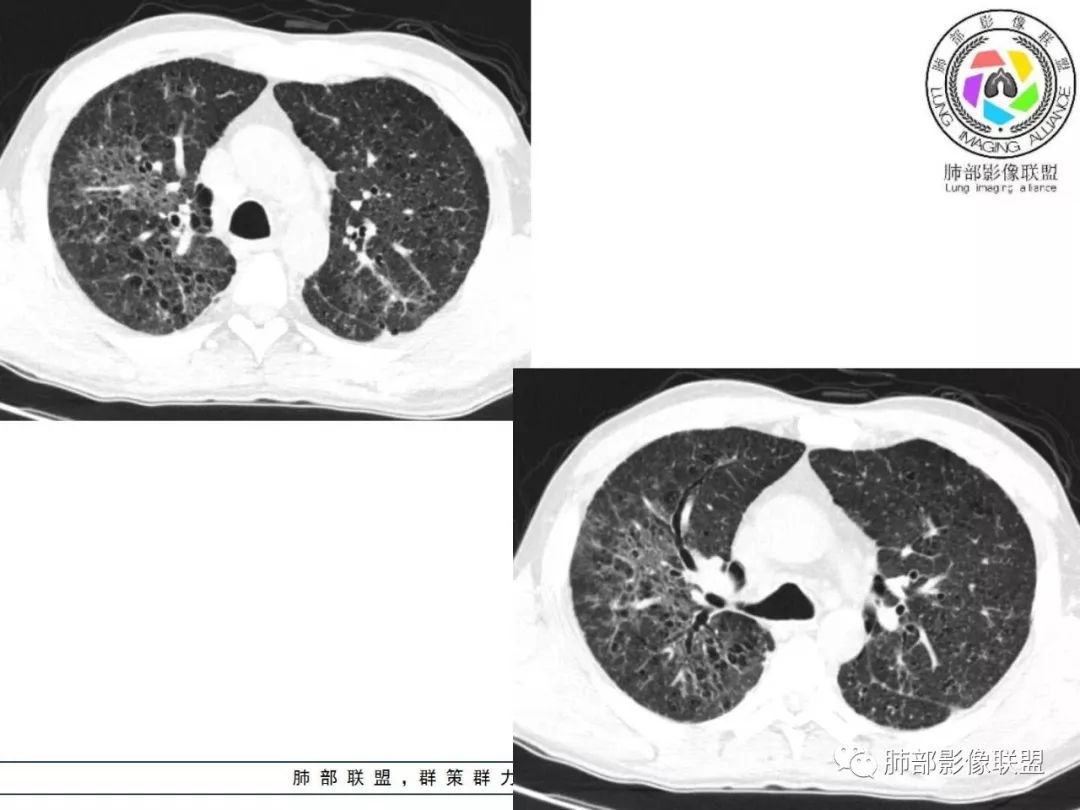

胸部CT:两肺弥漫病灶,磨玻璃影,少许实变,部分累及胸膜,磨玻璃区可见囊?少许胸腔积液,两肺可见结节,支气管血管束增粗,小叶间隔增厚,支气管走形有扭曲扩张,可见纤维化。气肿、大泡。考虑:感染性病变,PCP?查下HIV,CD4,G等。鉴别结核、结缔组织病肺浸润。

胸部CT:两肺弥漫病灶,中央间质分布为主,部分位于胸膜及叶间裂旁,磨玻璃影,斑片影,部分实性结节,肺气囊,支气管血管束增粗,小叶间隔增厚,叶间裂不均匀增厚,支气管走形有扭曲扩张,可见纤维化、气肿、大泡。考虑:LIP加MALT。鉴别PLCH、PCP、结核、结缔组织病肺浸润。

双肺弥漫性病变,多发磨玻璃密度及小叶间隔增厚,大部分沿支气管血管束分布,伴支气管轻度扩张,以午后及晚上发热为主,考虑感染性病变,间质性结核可能大,另双肺多发肺气囊,LIP待排

两肺弥漫病灶,中央间质分布为主,部分位于胸膜及叶间裂旁,磨玻璃影,斑片影,部分实性结节,肺气囊,支气管血管束增粗,小叶间隔增厚,叶间裂不均匀增厚。考虑:间质性肺病,LIP,鉴别OP

病灶呈片状磨玻璃密度影,呈典型的烟花征。磨玻璃影密度偏高,有网结节样改变,与正常肺实质分界清楚,且常见相对高密度的勾画。

病变一般沿血管支气管束分布或小叶分布,一般上肺多于下肺(这与常见继发性肺结核分布相若)。

常会伴有其他继发性肺结核病灶,如斑片影、结节影,树芽征,新旧不等改变。

2. 肺气肿背景(小叶中心性肺气肿);双肺多发病灶整体沿血管支气管束及胸膜下分布,以上叶及下叶背段分布为主,有实变及GGO,边界清楚,有树芽,小叶间隔及中央间质增厚,叶间裂见到多发结节,部分支气管不规则牵拉扩张,提示病灶纤维化明显,结合临床病史,考虑病灶为间质性感染,肺门及纵隔内有钙化淋巴结,小叶间隔结节,考虑淋巴道增值性疾病可能,综合常规要怀疑间质性肺结核。